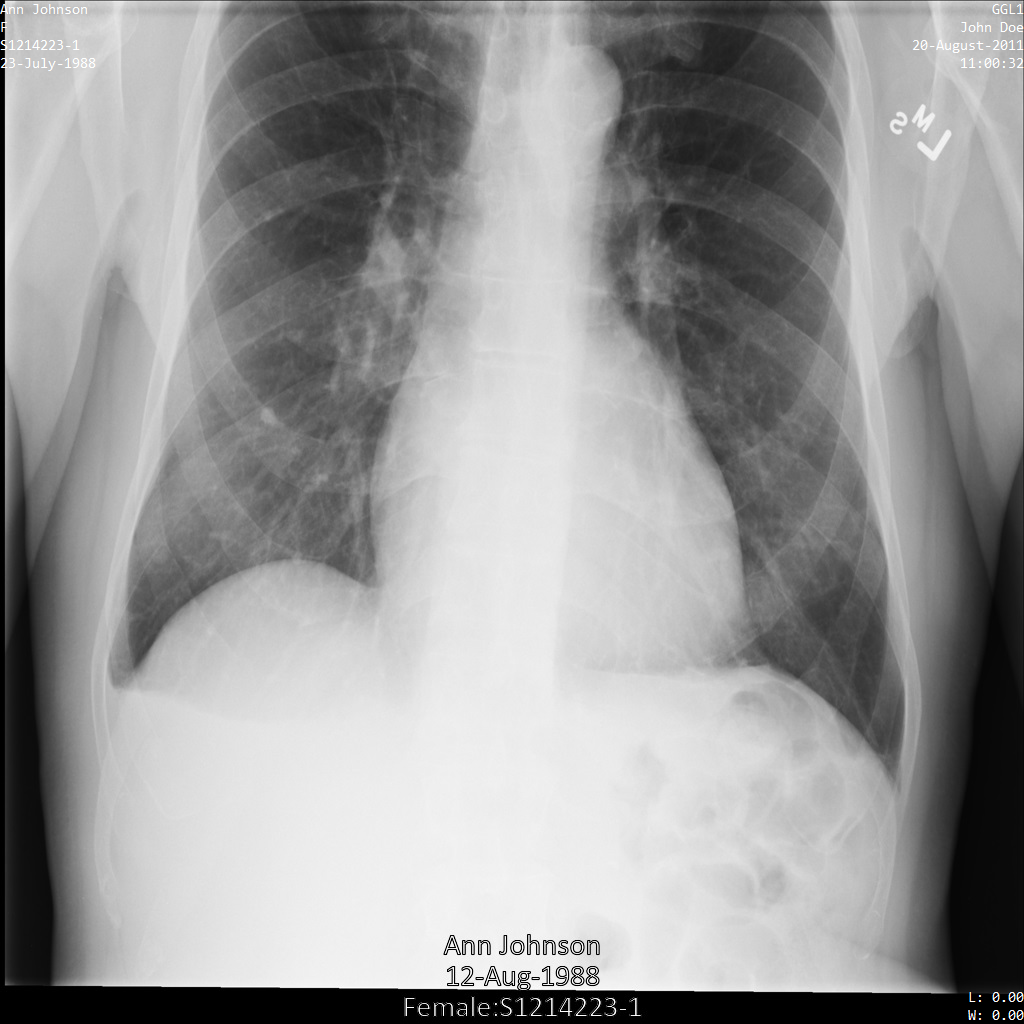

Después de enviar la imagen a la API de Cloud Healthcare, la imagen aparece de la siguiente manera. De las etiquetas proporcionadas en la removelist, solo se quita PatientBirthDate en la imagen, ya que es la única etiqueta de la lista de eliminación que corresponde a los metadatos visibles en la imagen.

Si bien PatientBirthDate en la esquina superior de la imagen se ocultó de acuerdo con la configuración de la removelist, la PHI de efecto quemado que se encuentra en la parte inferior de la imagen permanece. Para quitar también el texto quemado, consulta Cómo ocultar el texto quemado de las imágenes.

Después de enviar la imagen a la API de Cloud Healthcare mediante el perfil de filtro de etiqueta ATTRIBUTE_CONFIDENTIALITY_BASIC_PROFILE, la imagen aparece de la siguiente manera. Mientras se ocultan los metadatos que se muestran en las esquinas superiores de la imagen, permanece la PHI quemada que se encuentra en la parte inferior de la imagen.

Para quitar también el texto grabado, consulta Cómo ocultar el texto grabado de las imágenes.

Después de enviar la imagen a la API de Cloud Healthcare mediante la opción REDACT_ALL_TEXT, la imagen aparece de la siguiente manera. Mientras se quita el texto grabado en la parte inferior de la imagen, los metadatos en las esquinas superiores de la imagen permanecen. Para quitar también los metadatos, consulta Desidentifica las etiquetas de DICOM.

Después de enviar la imagen a la API de Cloud Healthcare mediante las opciones REDACT_ALL_TEXT y DEIDENTIFY_TAG_CONTENTS, la imagen aparece de la siguiente manera. Observa los siguientes cambios:

- Los nombres en la esquina superior izquierda y en la esquina superior derecha de la imagen se transformaron con una

CryptoHashConfig - Las fechas en la esquina superior izquierda y derecha de la imagen se transformaron con un

DateShiftConfig - Se oculta el texto grabado que aparece en la parte inferior de la imagen.

Después de enviar la imagen a la API de Cloud Healthcare mediante el perfil DEIDENTIFY_TAG_CONTENTS, la imagen aparece de la siguiente manera.

Observa los siguientes cambios:

- Los nombres en la esquina superior izquierda y en la esquina superior derecha de la imagen se transformaron con una

CryptoHashConfig - Las fechas en la esquina superior izquierda y derecha de la imagen se transformaron con un

DateShiftConfig